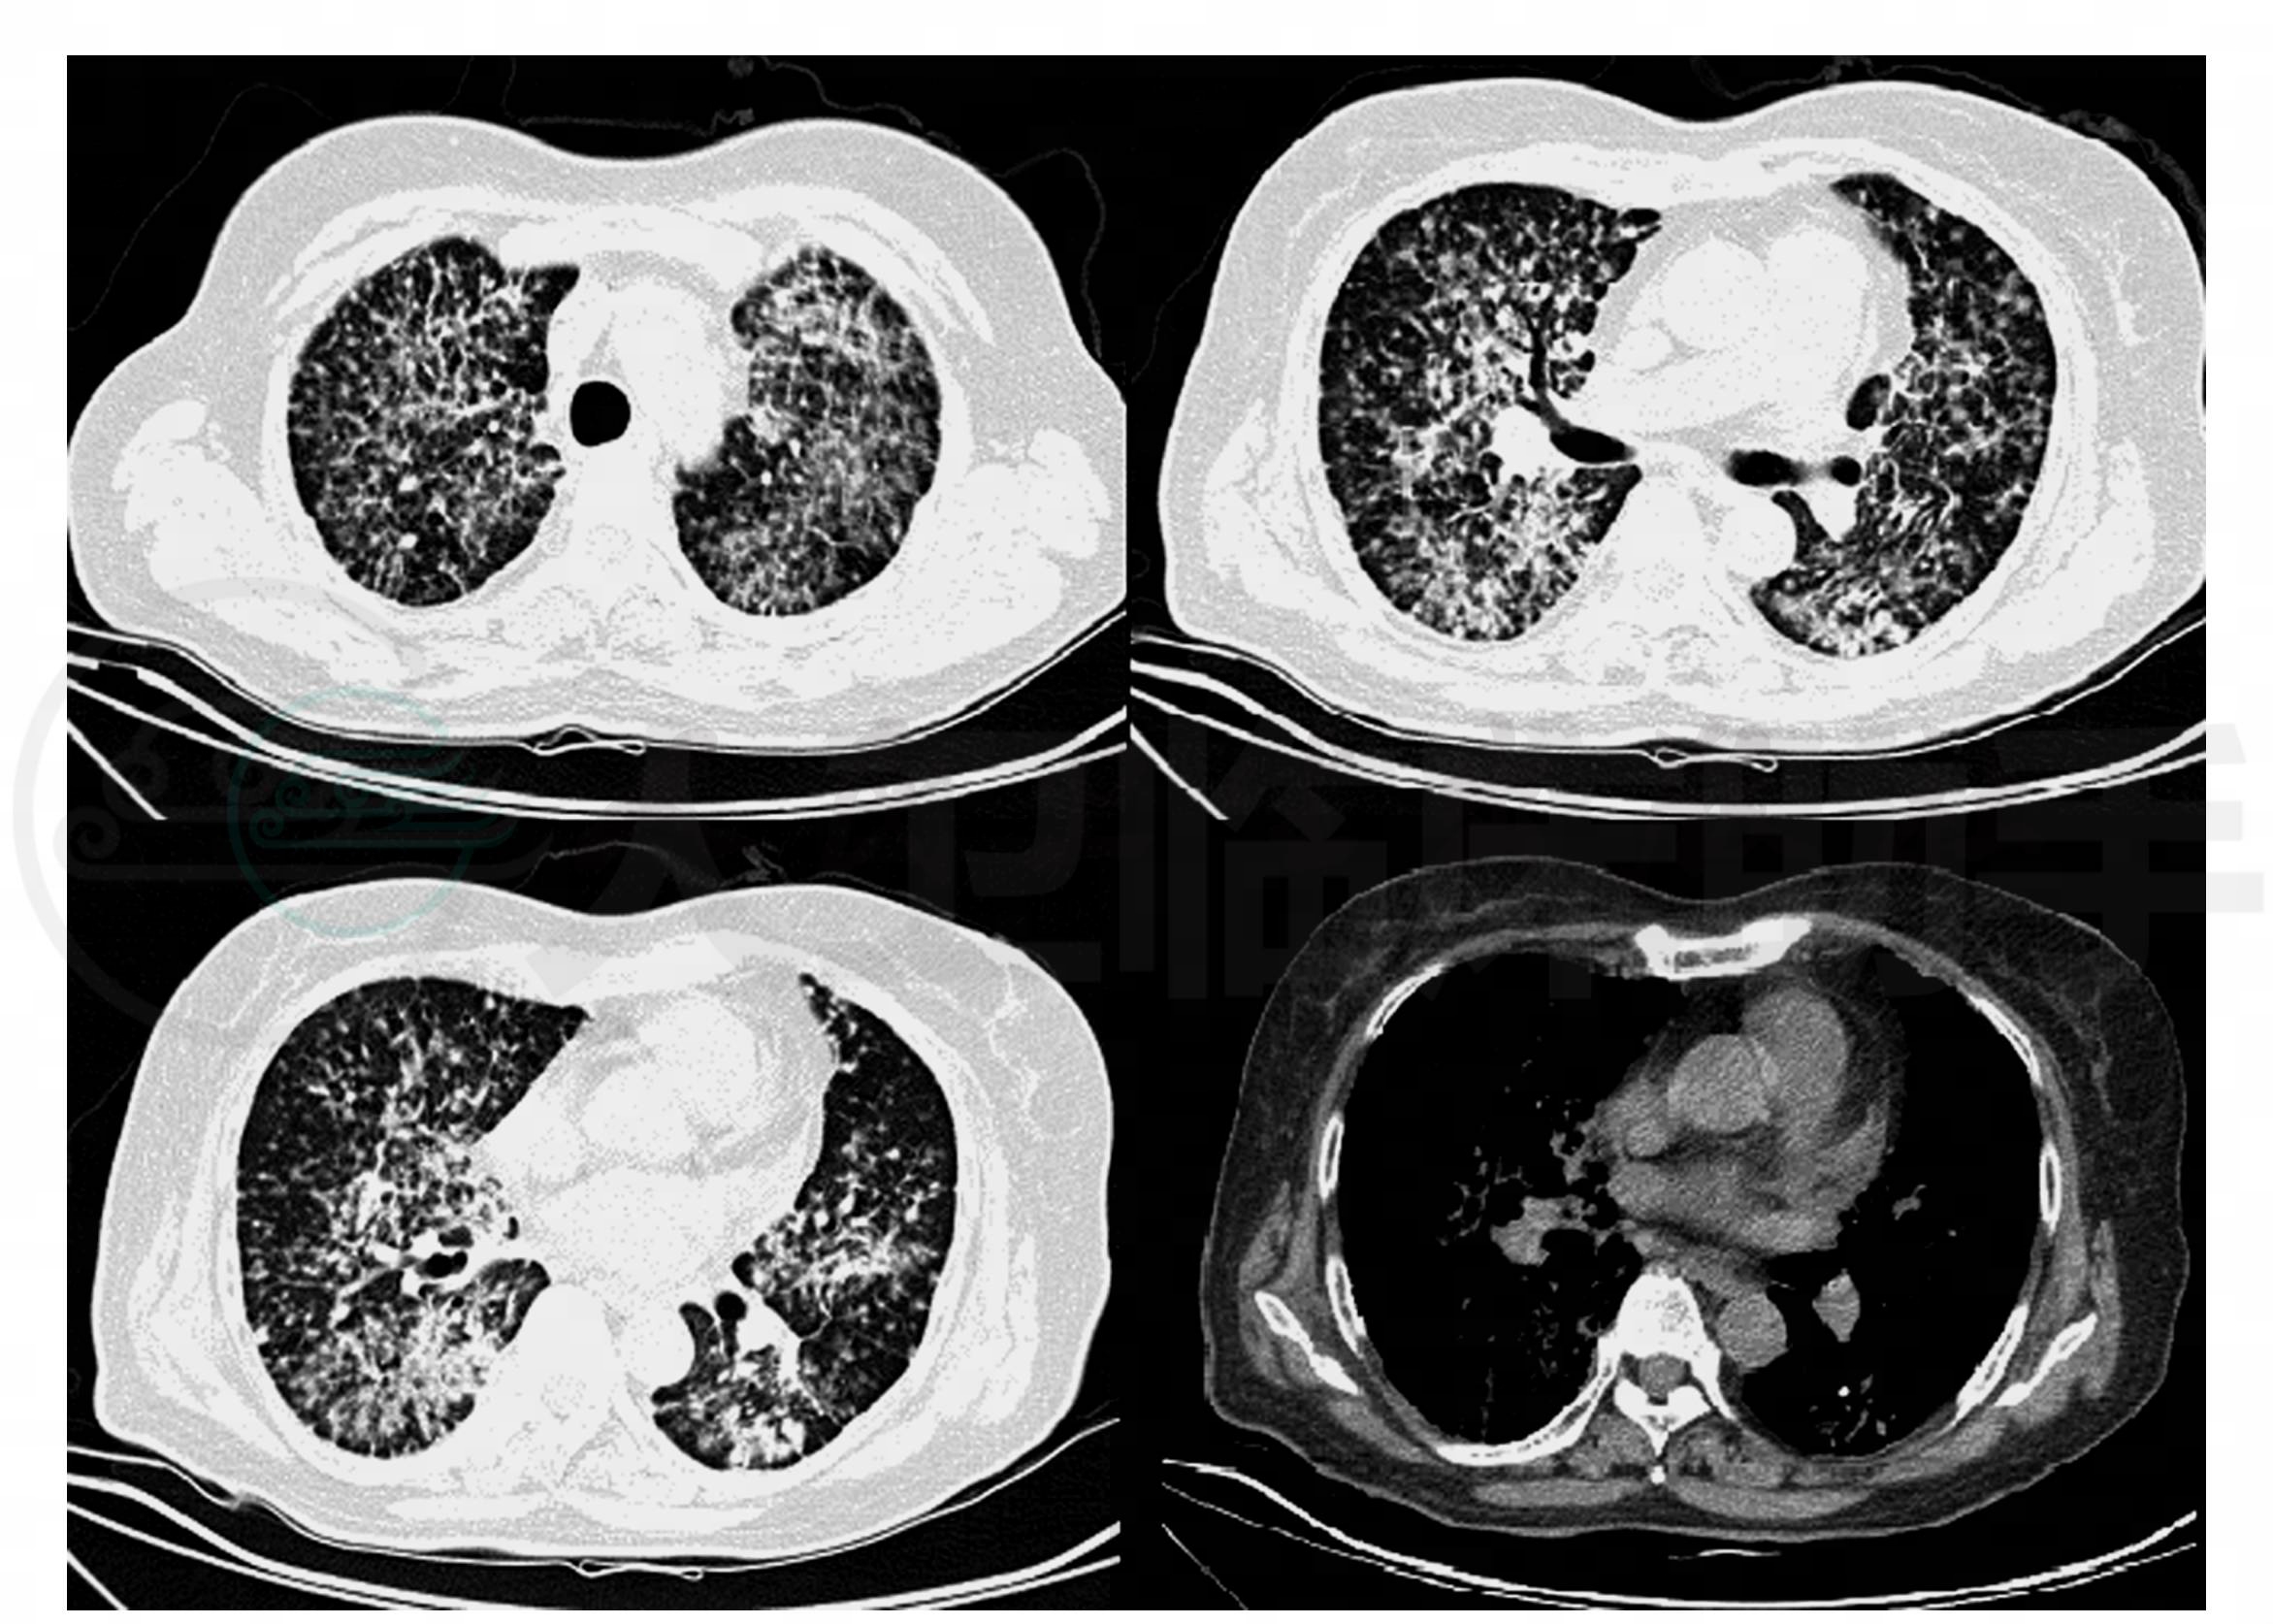

入院时辅助检查:血常规:WBC 16.5×109/L,NE%69.2%,HB 138g/L,PLT 282×109/L;肺CT:双肺弥漫分布大小不等结节影,部分结节影呈磨玻璃密度,部分呈“树芽”征,部分结节密度较致密,部分结节融合,结节分布不均,小叶间隔增厚,左肺下实变影内见钙化,肺内多发钙化结节,纵隔见多组钙化小淋巴结(图1)。

图1 双肺弥漫分布大小不等结节影,部分结节影呈磨玻璃密度,部分呈“树芽”征,部分结节密度较致密,部分结节融合,结节分布不均;小叶间隔增厚,左肺下实变影内见钙化